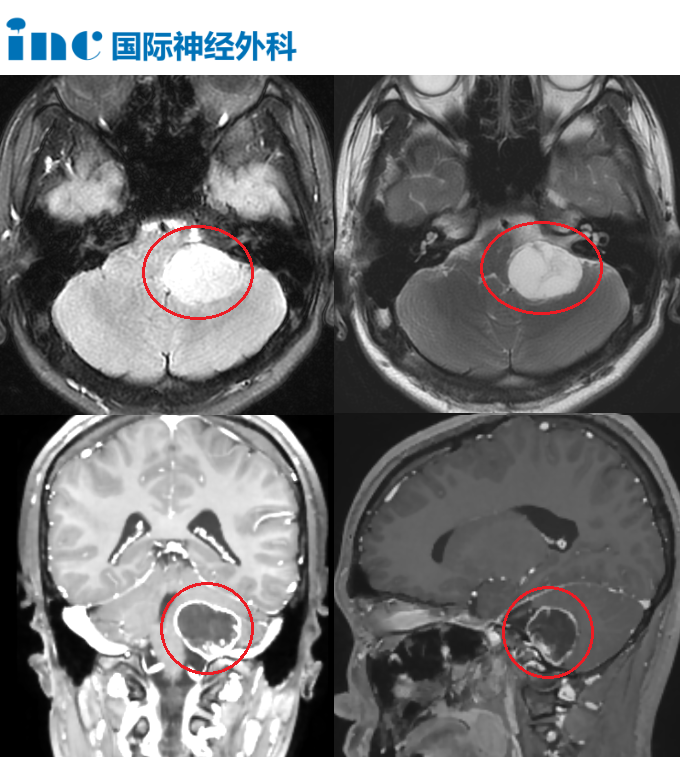

人在情绪激动或大声说话时容易声音嘶哑,似乎是一个十分常见的现象,然而,当这件事发生在15岁的沫沫身上时,一切都发生了翻天覆地的变化。 不久后,沫沫开始出现头痛、扁桃体发炎、耳...